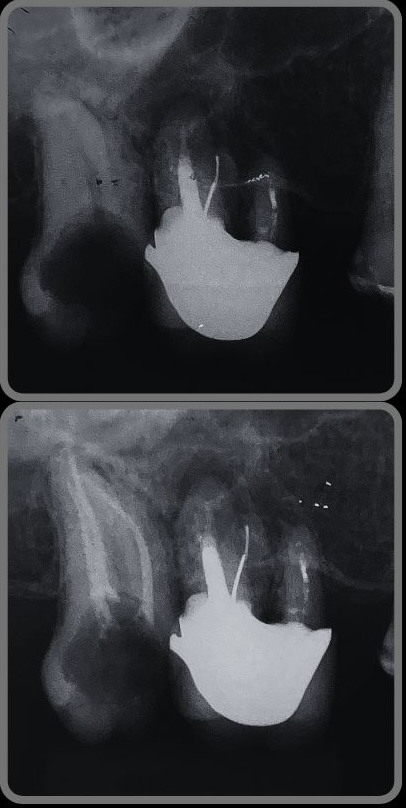

Veja alguns casos de sucesso